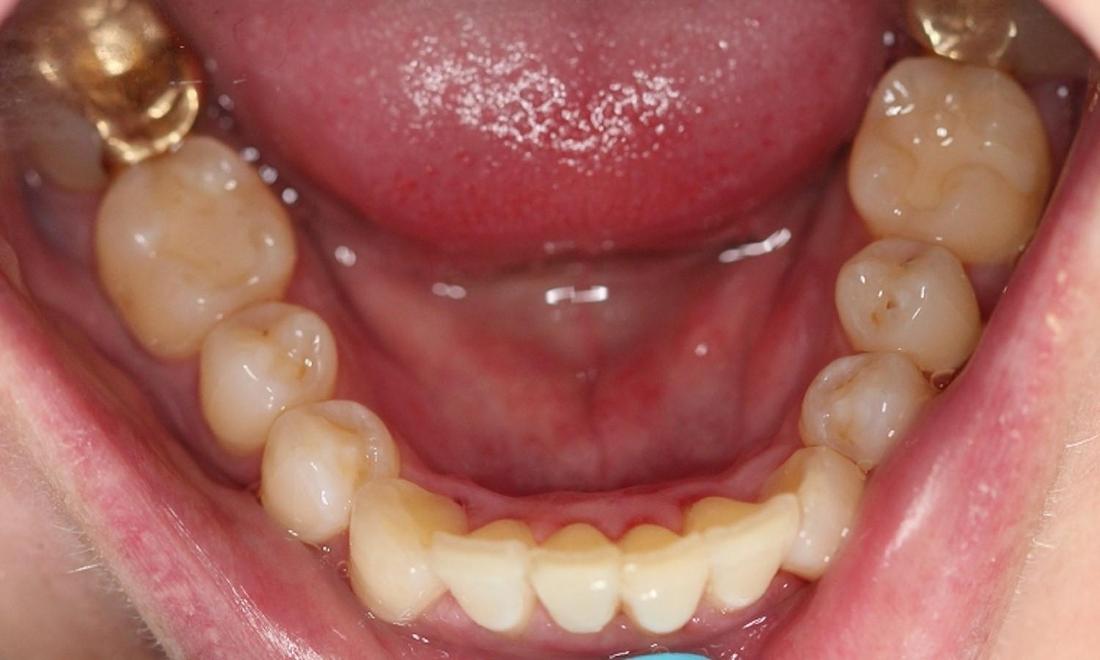

This patient's crowded teeth were posing a few different risks including plaque and tartar buildup which can harbor harmful periodontal bacteria, risk of periodontal disease, tooth, and bone loss. After two years of Invisalign treatment, teeth have aligned properly for a healthier mouth.

crowded lower teeth before an invisalign treatment | invisalign dentist in vienna va aligned lower teeth after an invisalign treatment | dentist invisalign vienna